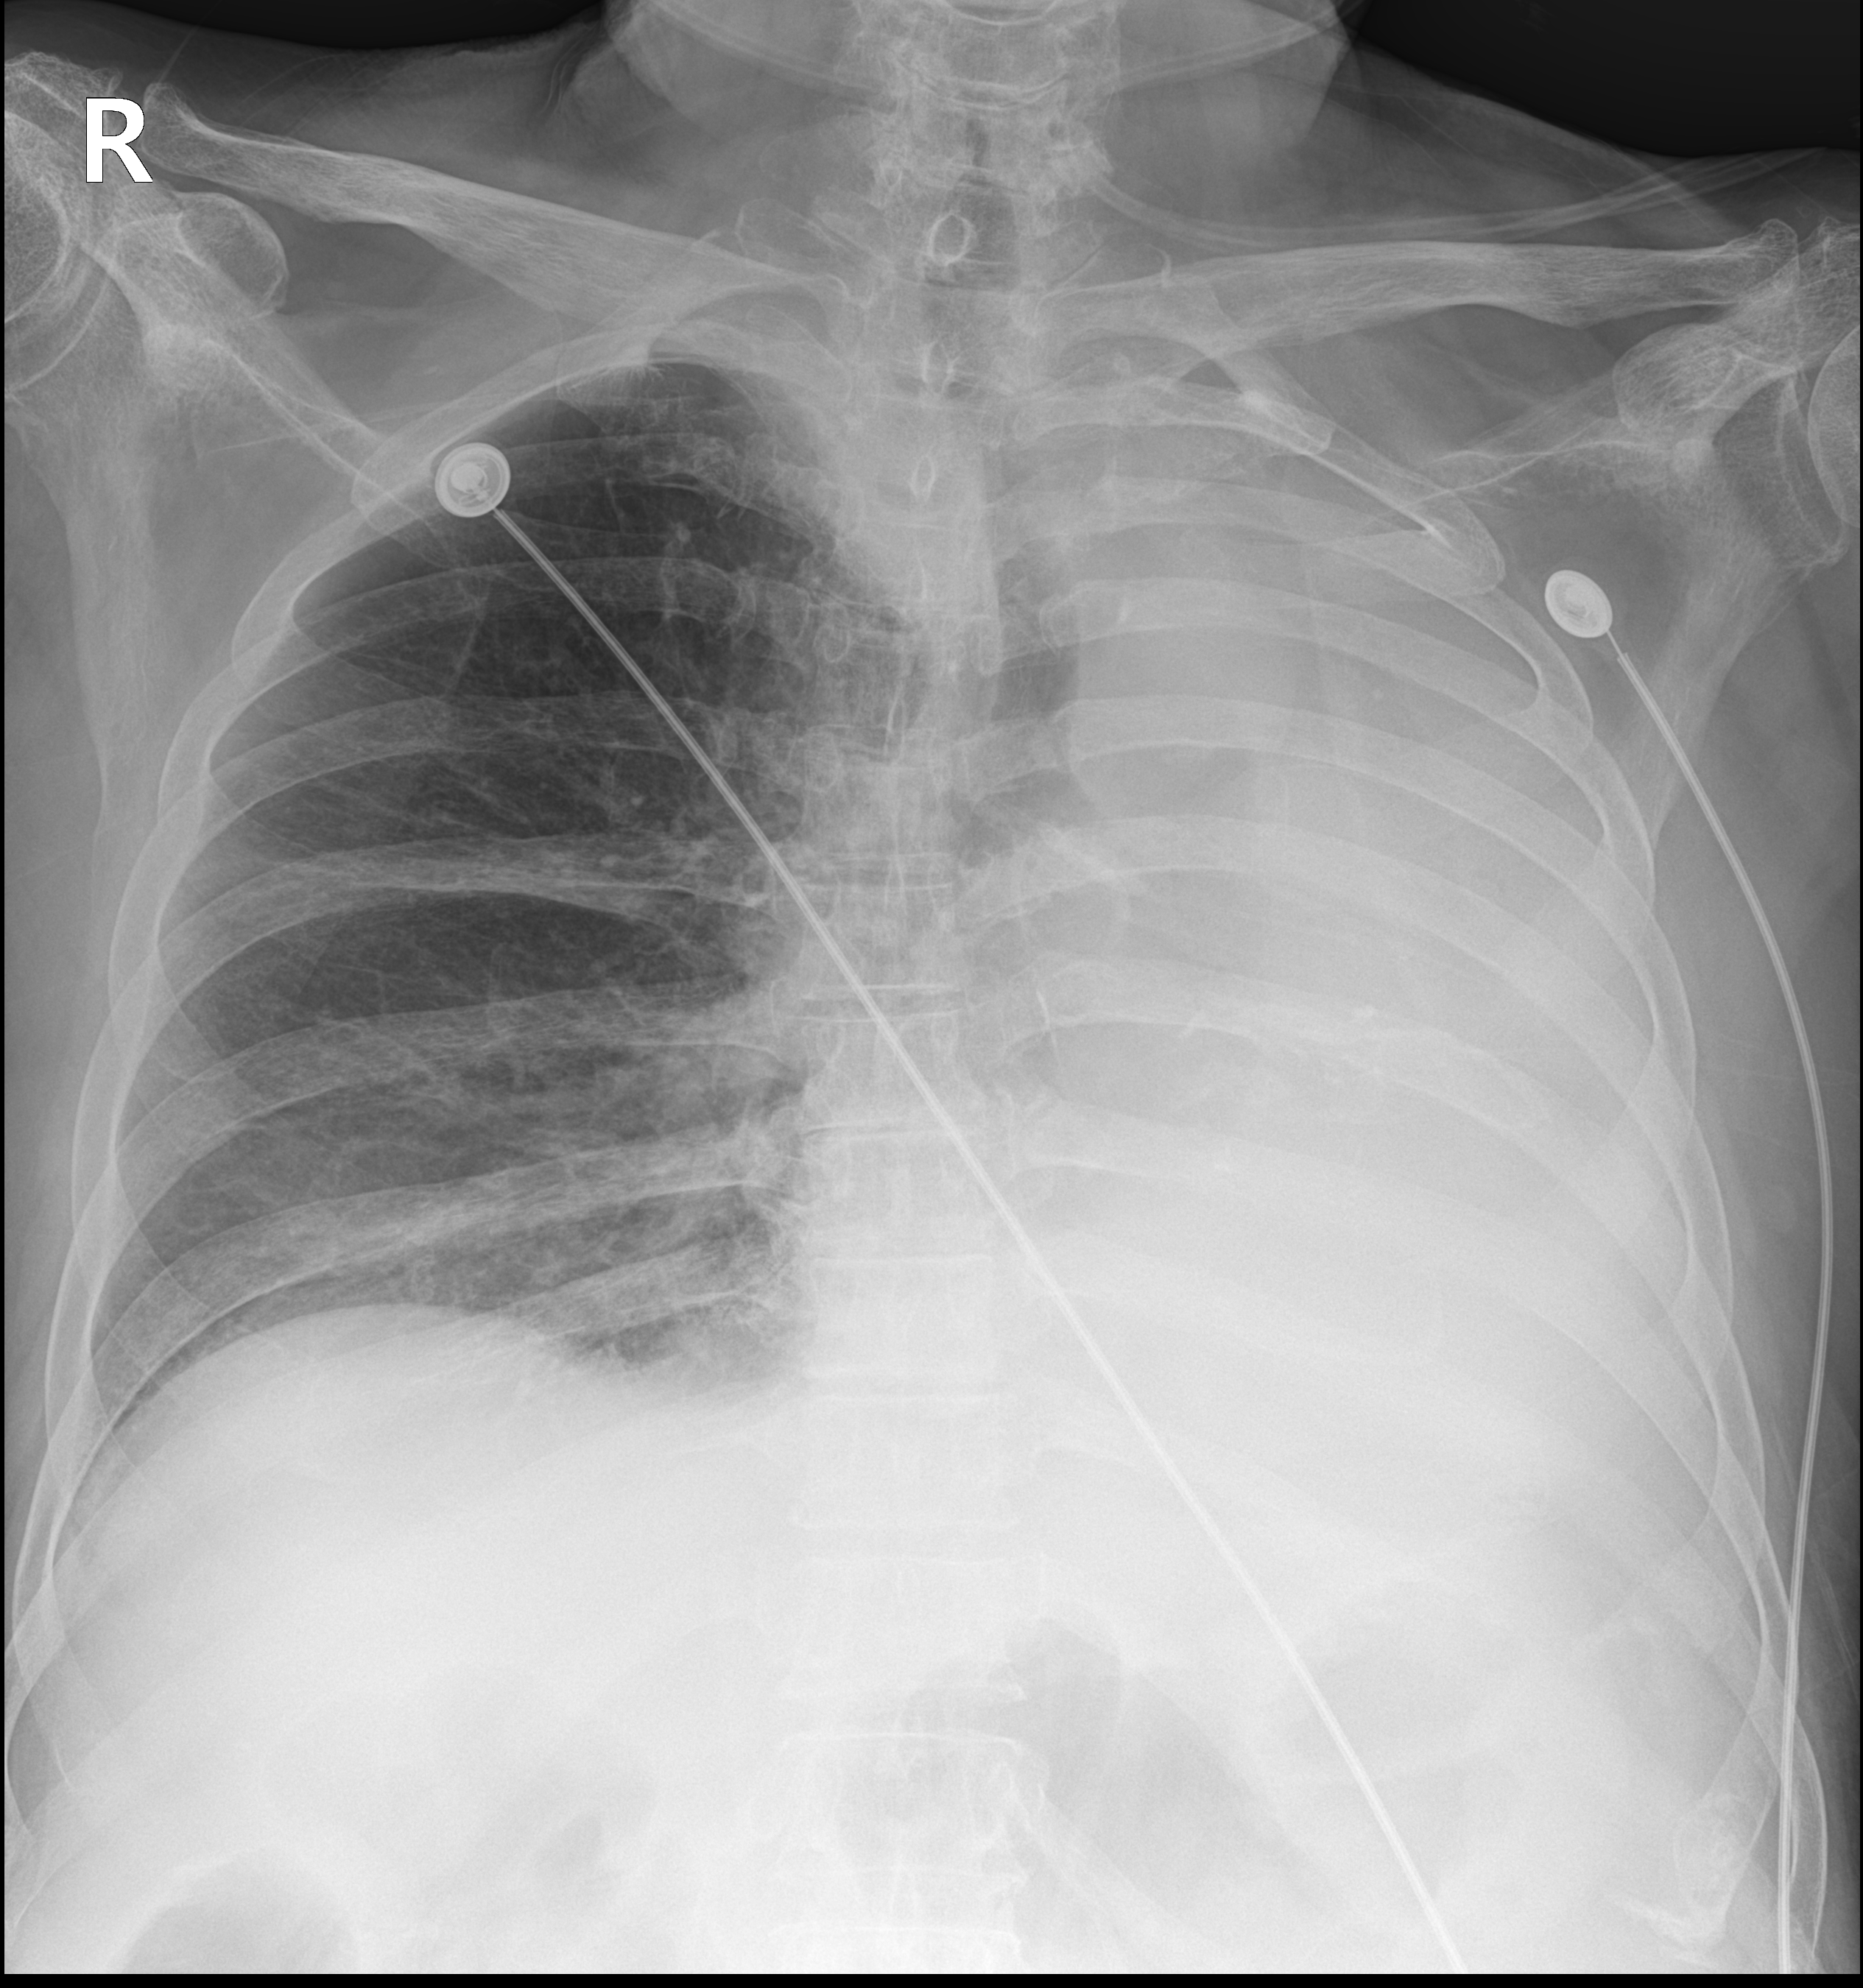

시행한 환자의 chest AP 사진이다.

사진을 보면 환자의 좌측 폐가 있어야 할 공간(사진의 우측이 환자의 좌측)이 하얗게 변해 있음을 알 수 있다.

기관이 좌측으로 편위(deviation)되어 있으며, 좌측 폐가 약간 쪼그라들어 보이는 소견을 보았을 때 무기폐를 의심해 볼 수 있는 상태였다.